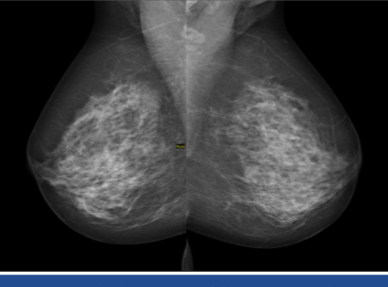

mammography

radiographic technique used to screen for breast cancer

can reveal cancer before even palpable

incidence of breast cancer in women

1 in 8

women diagnosed w/ breast cancer in 2021

284,000

breast cancer screening recommendations

every year for women 40+

self-examination once a month

clinical breast exam 19+